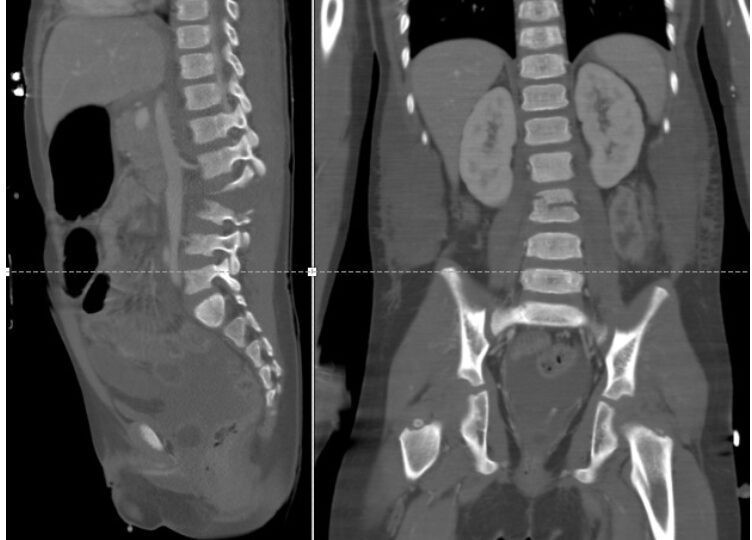

CIR - graus trauma renal

1 - contusões e hematomas subcapsulares

2 - lacerações corticais com hematomas perirrenais

3 - laceração cortico-medular ou trombose arterial segmentar

4 - laceração sistema coletor, lesões pedículo principal

5 - avulsão hilo renal